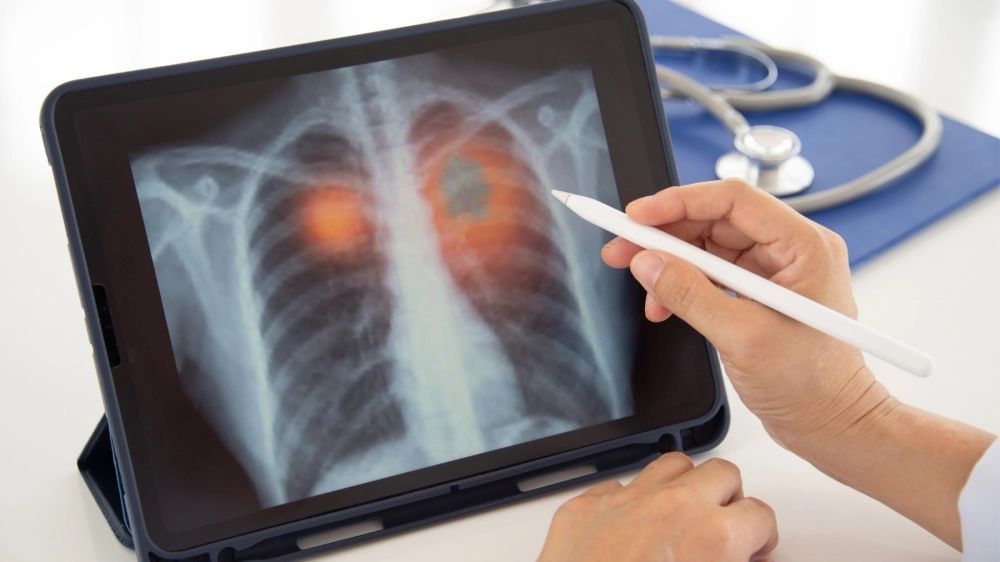

Tầm quan trọng của việc chụp X-quang phổi